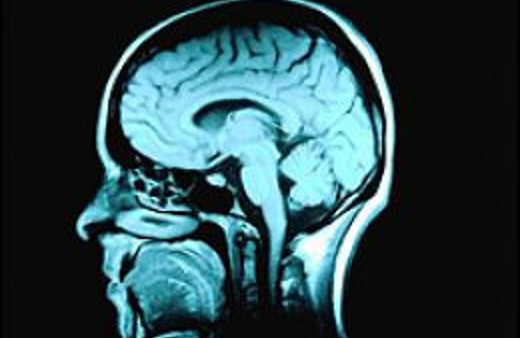

Alzheimer Hastalığı